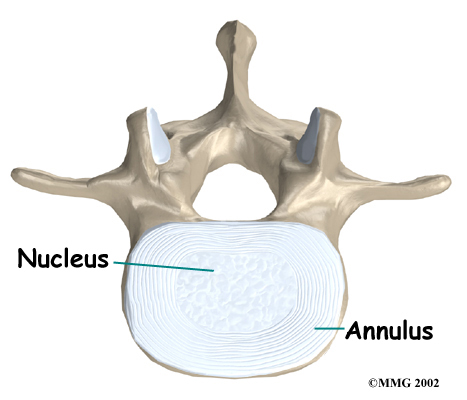

An intervertebral disc fits between each vertebral body and provides a space between the spine bones. The disc normally works like a shock absorber. It protects the spine against the daily pull of gravity. It also protects the spine during heavy activities that put strong force on the spine, such as jumping, running, and lifting.

An intervertebral disc is made up of . The center, called the nucleus, is spongy. It provides most of the ability to absorb shock. The nucleus is held in place by the annulus, a series of strong ligament rings surrounding it. Ligaments are strong connective tissues that attach bones to other bones.